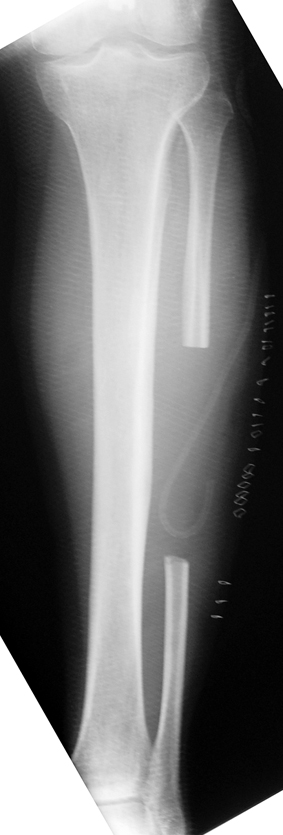

Case 3